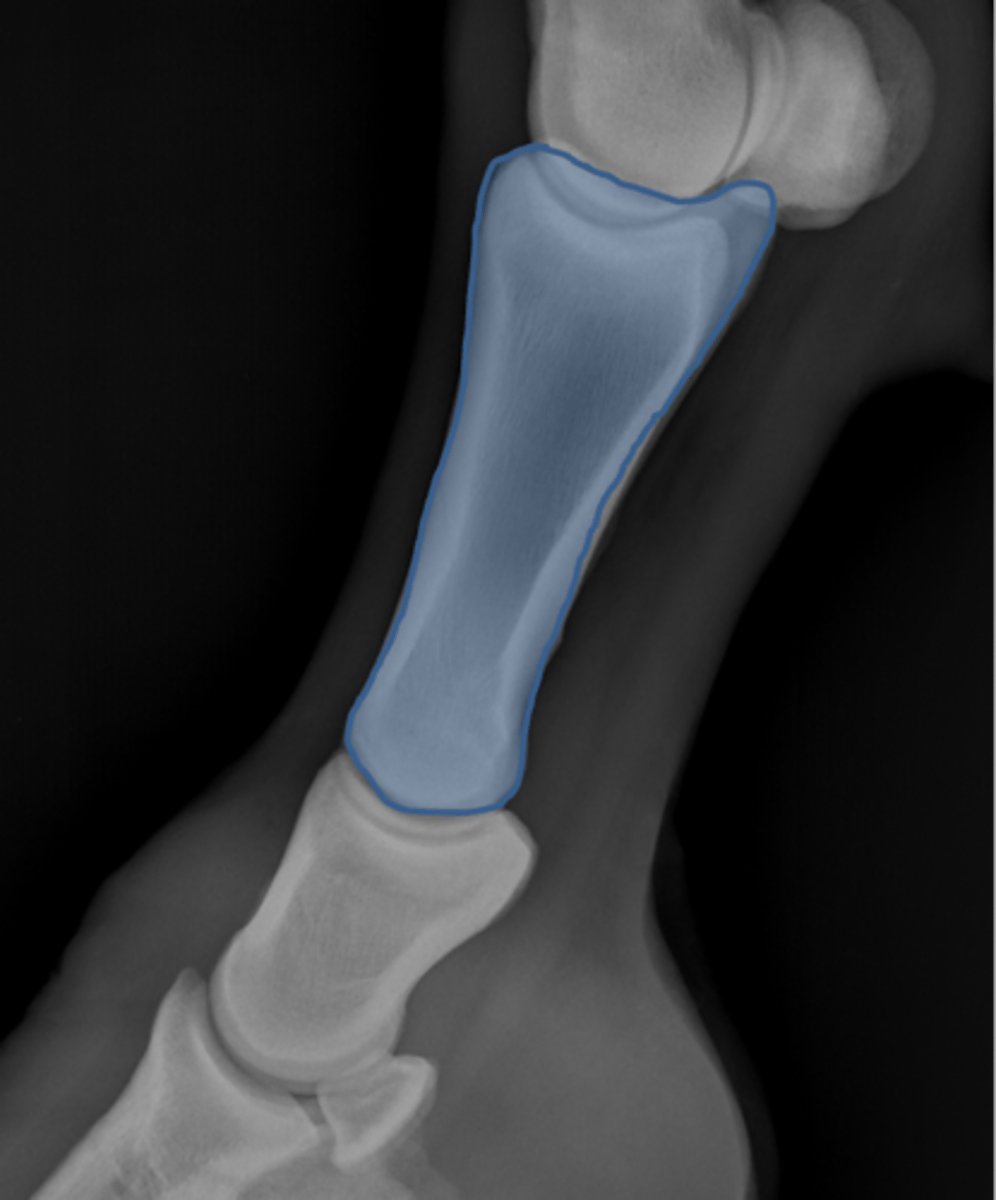

Short pastern (P2)

Long pastern (P1)

Pastern joint (proximal interphalangeal joint)

Long pastern (P1)

Short pastern (P2)

Medullary cavity

Ergot

Collateral ligament of the coffin joint

What attaches at EOP?

Nutrient foramen of P2

Extensor process of P3

Proximal sesamoid bone

Sagittal ridge

Condyles of third metacarpal bone

Palmar process of P2

Proximal sesamoid bones

Sagittal ridge

Attachment of collateral ligaments